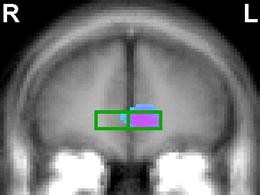

The group by stimulus-condition interaction was significant (p<0.01) for amygdala activation, with the greatest effects in the happy face condition. Relative to HC, amygdala increases were greater in unmedicated BD, but lower in medicated BD. Rostral anterior cingulate (rAC) activation was decreased in unmedicated BD compared to HC; however, BD participants taking medication demonstrated rAC activation similar to HC participants.

Although the sample sizes were small, these preliminary results suggest that BD is associated with increased amygdala and decreased rAC response to emotional faces. The findings also provide preliminary evidence that mood-stabilizing medications may reverse abnormalities in BD in the response of an amygdala–frontal neural system to emotional stimuli.